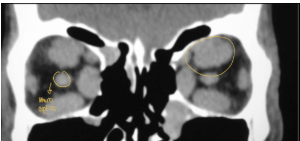

qué esperas ver en una TC por exoftalmos

protrusión ocular anormal, Disociación índice globo ocular-línea intercigomática (Si línea no cruza los ojos es anormal)

¿de qué enfermedad nos habla la siguiente imagen?

retinoblastoma bilateral y cuadrilateral